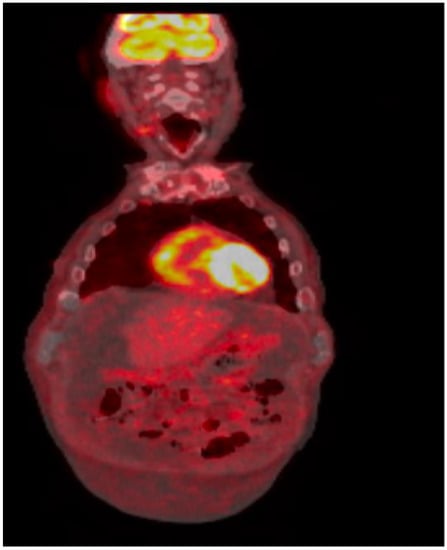

Repeat bone marrow biopsy showed hypercellular marrow with persistent/recurrent involvement by CLL with 35% lymphocytes (Figure 2 and Figure 3). Flow cytometry analysis on bone marrow showed the presence of aberrant clonal B cells (~14% of total events) with the following immunophenotype positive for CD5, CD19, CD20 (dim), CD22, CD23 (subset), CD45, HLA-DR, CD11c (subset), surface Lambda light chain (dim) with a Kappa to Lambda ratio of <1:10 and negative for CD10, CD103, FMC-7, CD38, and surface Kappa light chain. Molecular studies on the bone marrow aspirate did not detect the deletion of 13q, ATM/11q, or TP53 mutation, but was positive for trisomy 12.

Figure 3. Hypercellular bone marrow with trilineage hematopoiesis as well as increased lymphocytes.